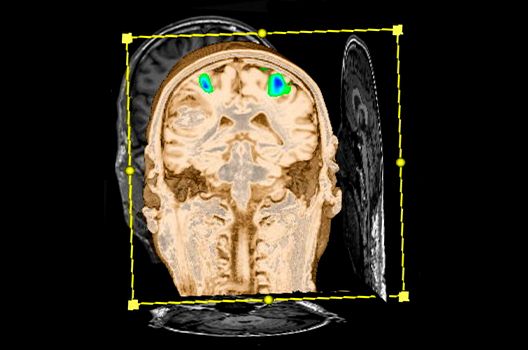

- Funktionelle Bildgebung des Gehirns (fMRT)

Die Magnetresonanztomographie (MRT) ist ein Verfahren, bei dem durch magnetische Kräfte Bilder des Körperinneren angefertigt werden. In der Neuroradiologie können manchmal kleinste Veränderungen schwere Folgen haben; daher forschen wir an der Entwicklung hochauflösender MRT-Sequenzen, mit denen diese Prozesse und auch einzelne Nervenfaserbahnen sichtbar gemacht werden können. Darüber hinaus sind bei vielen Erkrankungen des Gehirns die Blutgefäße betroffen. Daher arbeiten wir an der Neu- und Weiterentwicklung von MRT-Sequenzen zur Darstellung der Blutgefäße und zur Blutflussanalyse (sog. „Angio-MRT“). Einen besonderen Forschungsschwerpunkt unserer Klinik stellen die MR-Protonenspektroskopie und die funktionelle MRT dar, mit denen die Analyse einzelner chemischer Substanzen im Hirngewebe oder die Darstellung ausgewählter Hirnfunktionen möglich ist.